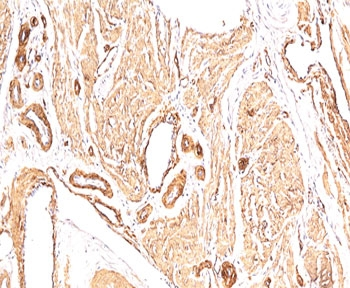

IHC: Formalin-fixed, paraffin-embedded Leiomyosarcoma stained with Smooth Muscle Actin antibody (clone SPM332).